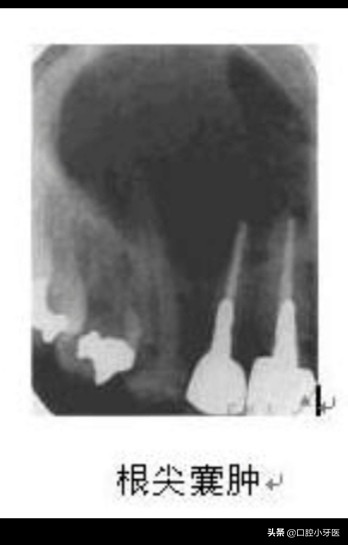

如果这两种情况没有及时的处理,那么将会发生比较严重的根尖周囊肿,根尖周囊肿是这三种情况当中最严重的,可能的原因是由于根尖周肉芽肿中心部位的血运不足,中心发生化脓液化变大,变成根尖周囊肿,根尖周囊肿体积较大对颌骨造成破坏,在影像学上显示出低密度的影像,边缘界限清晰!